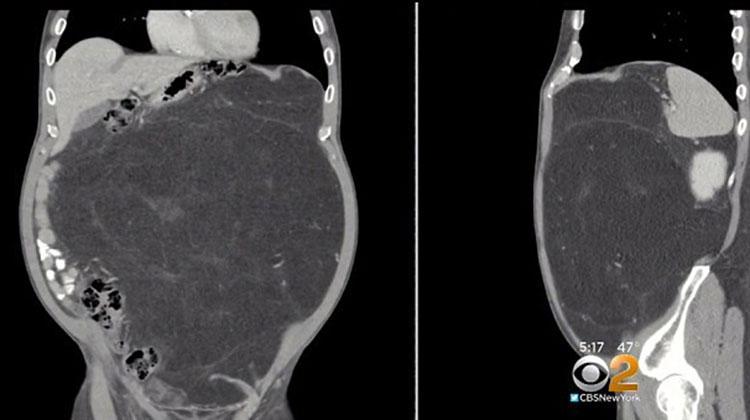

Vào tháng 12/2017, ông thuyết phục bác sĩ thực hiện một cuộc kiểm tra cắt lớp, bất chấp sự ngăn cản của công ty bảo hiểm. Khi nhìn ảnh chụp, tất cả mọi người đều choáng váng khi phát hiện khối u cỡ lớn nằm trong khoang bụng của ông.

Các bác sĩ chẩn đoán ông bị mắc căn bệnh u mỡ (Liposarcoma) - khối u lành tính, được tạo nên bởi một lớp chất béo dày tích tụ bên dưới da, nằm giữa da và lớp cơ. Liposarcoma phát triển từ các tế bào mỡ tại bất cứ cơ quan nào trong cơ thể, nhưng phổ biến nhất vẫn là ở bụng và chân tay.

Trong quá trình thực hiện phẫu thuật cắt bỏ lớp u mỡ, các bác sĩ phát hiện lớp mỡ đã lan rộng, quấn quanh một bên thận của ông Kevin. Bác sĩ Julio Teixeira, người trực tiếp cắt lớp u cho biết: “Khối u mỡ nặng tới hơn 12kg. Nó chính là khối u lớn nhất mà tôi từng thấy. Có lẽ nó đã mất khoảng 10-15 năm mới có thể lớn đến như vậy”.